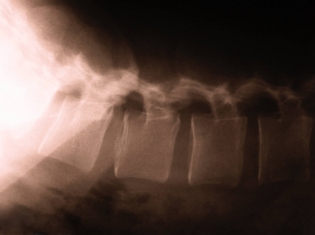

Inside of bones are cells that must continue to generate replacement bone tissue to keep bones from becoming brittle. Old bone cells are absorbed back into the body as new ones form.

This cycle of reabsorption of old cells and generation of new cells is vital to maintaining proper bone structure. Osteoporosis is a condition of weak bone structure that can result in bone fractures from even very minor accidents.